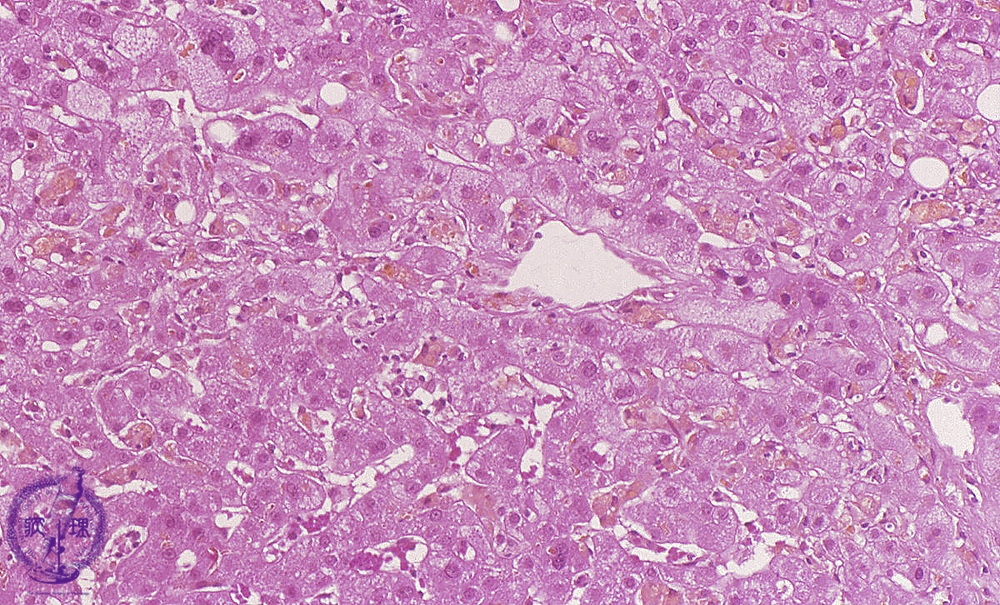

• (10)Cholestatic disease (acute drug-induced)

Microscopic image (HE stain, high power): In addition to centrilobular balloon cell degeneration and multiple scattered bile duct plugs, there are mildly swollen Kupffer cells and focal hepatocellular necrosis.